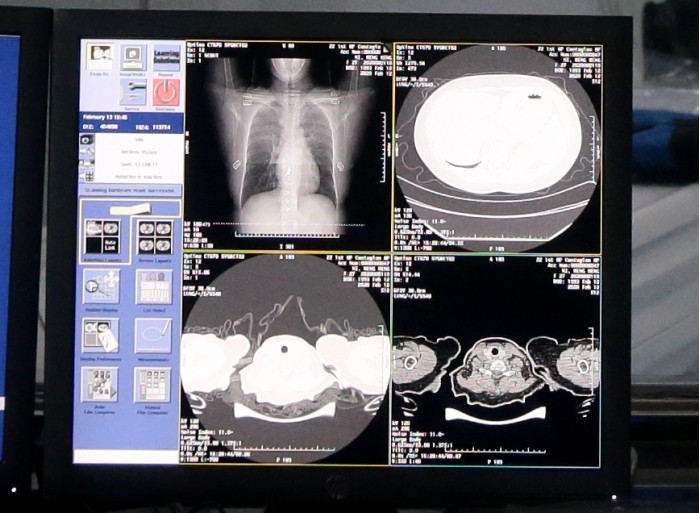

AI自动识别新冠肺炎病例CT胸片

根据国家卫健委公布的诊疗方案第五版,临床诊断无需依赖核酸检测结果,CT影像临床诊断结果可作为新冠肺炎病例判断的标准。新冠肺炎患者的CT胸片的影像特征表现为单肺或双肺多发、斑片状或节段性磨玻璃密度影等细微变化。一位新冠肺炎病人的CT影像大概在300张左右,这给医生临床诊断带来巨大压力,医生对一个病例的CT影像肉眼分析耗时大约为5-15分钟。

医护人员使用AI识别新冠肺炎病例CT影像

达摩院医疗AI团队基于当前最新的诊疗方案、钟南山等多个权威团队发表的关于新冠肺炎患者临床特征的论文,与多家机构合作,基于5000多个病例的CT影像样本数据,学习训练样本的病灶纹理,研发了全新的AI算法模型。通过NLP自然语言处理回顾性数据、使用CNN卷积神经网络训练CT影像的识别网络,AI可以快速鉴别新冠肺炎影像与普通病毒性肺炎影像的区别,最终识别准确率高达96%。AI每识别一个病例平均只需要不到20秒,大大提高诊断效率,减轻医生压力。